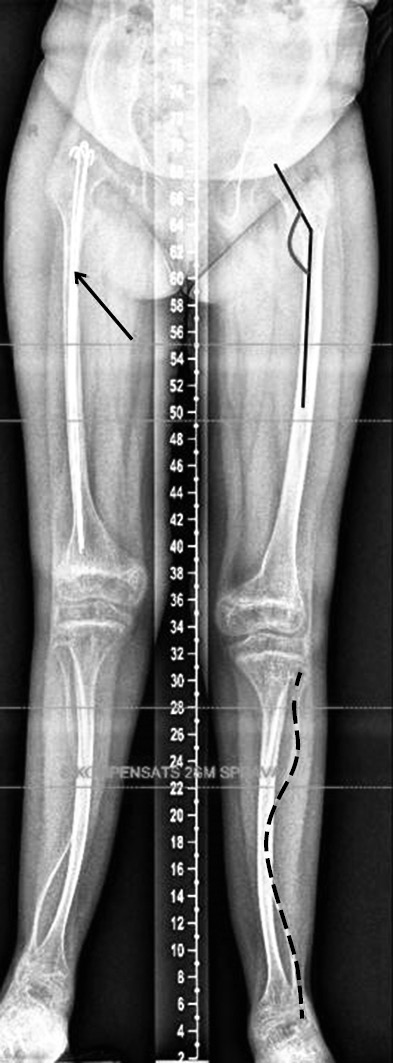

Radiographs of patient 1’s lower extremities revealed an increase in the neck–diaphyseal angle, a “serpentine” curvature of the fibula, and intramedullary reinforcement with spokes in the right femur after fracture (Fig. 4).

Fig. 4. Radiograph of the lower extremities of patient 1 in the standing position (panoramic) in direct projection: increased neck–diaphyseal angle (black line), “serpentine” curvature of the fibula (black dashed line), and intramedullary reinforcement with spokes of the right femur after fracture (arrow)